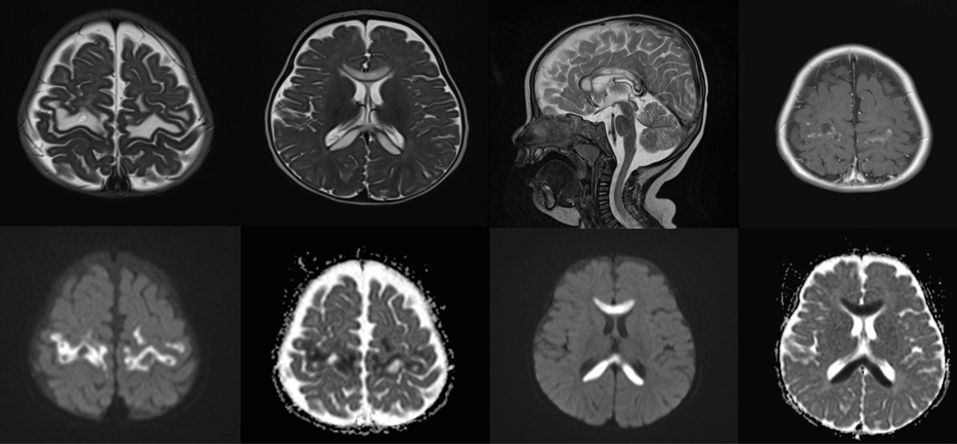

1 yaş erkek, hipotoni, beslenme güçlüğü ve gelişimsel gerilik

Myotonic distrofi

Hipoksik iskemik ensefaltopati

Akçaağaç şurubu idrar hastalığı (MSUD)

POLG ilişkili mitokondriyal hastalık spektrumu

PolG ilişkili hastalık ( mitokondriyal)

MSUD (Akçaağaç Şurubu Hastalığı)

polg related disorders

Lizensefali(pakigria spektrumu)

POLG ilişkili hastalıklar

Alpers Sendromu (Polg mutasyonu)

Pelizaeus-Merzbacher hastalığı

POLG- related disorder

POLG ilişkili mitokondrial hastalık

Molibden Kofaktör Eksikliği

Üre siklus defekti

Hipoksik iskemik beyin hasarı

Alpers-Huttenlocher sendromu (POLG ilişkili mitokondriyal hastalık)

POLG-related disorder

MSUD

POL-G İlişkili Mitokondriyal Hastalık

krabbe hastalığı

Tümefaktif ms lezyonları